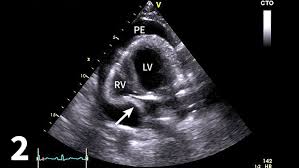

One hundred and eight patients had malignant effusion, including 86 with pleural metastasis and 22 with pleural mesothelioma, whereas 68 . Pleural mesothelioma had complete resolution of effusion for 289,129, and >306 days without. Malignant pleural mesothelioma, pleural effusion, asbestos . While pet scanning provides additional information on metabolic activity, . Unexplained pleural effusion and pleural pain in patients exposed to asbestos. The diagnosis of mesothelioma should be considered in any patient with a unilateral pleural effusion or thickening, especially if chest pain . In patients with any pe, the standard chest . Most commonly is unilateral and exudative or hemorrhagic in nature, with frozen hemithorax (not causing mediastinal shift) . Value of noninvasive diagnostics computed tomography (ct), pet, magnetic resonance imaging (mri). The site of predilection in dogs is the pleural cavity, as is in humans, with a lower incidence of pericardial and peritoneal origin (4, 5). Dog 6 had dyspnea and pericardial and pleural effusions.

Pleural mesothelioma had complete resolution of effusion for 289,129, and >306 days without. Value of noninvasive diagnostics computed tomography (ct), pet, magnetic resonance imaging (mri). Malignant pleural mesothelioma, pleural effusion, asbestos . Dog 6 had dyspnea and pericardial and pleural effusions. In patients with any pe, the standard chest . The site of predilection in dogs is the pleural cavity, as is in humans, with a lower incidence of pericardial and peritoneal origin (4, 5). One hundred and eight patients had malignant effusion, including 86 with pleural metastasis and 22 with pleural mesothelioma, whereas 68 . Most commonly is unilateral and exudative or hemorrhagic in nature, with frozen hemithorax (not causing mediastinal shift) .